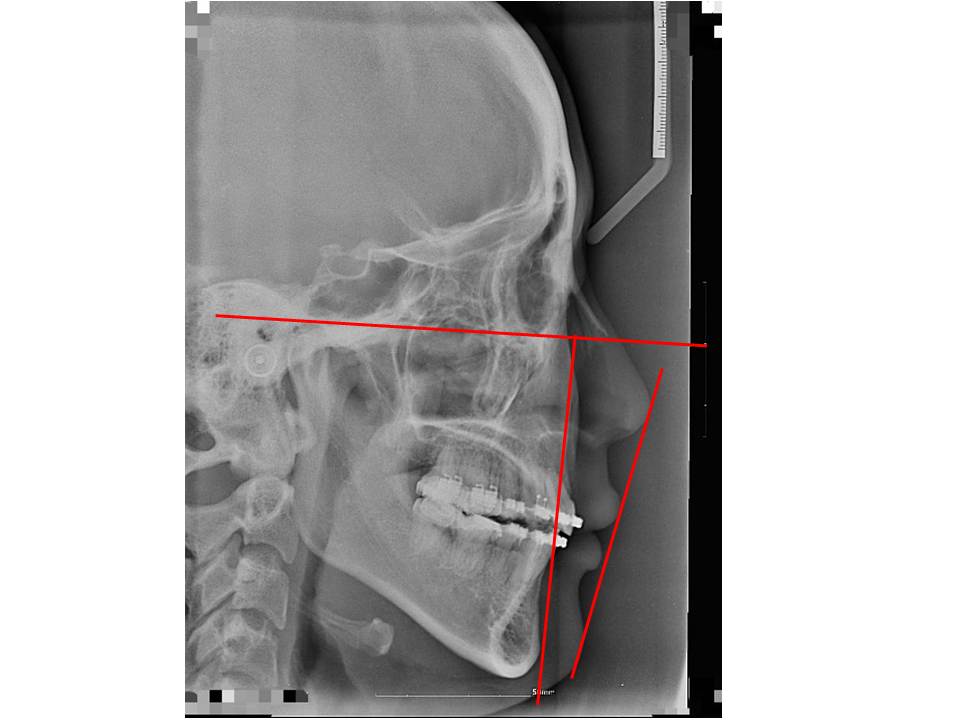

치아교정

세팔2.bmp 전에 잇몸뼈 돌출인 것 같다 하셨는데요. 그럼 혹시나 발치 후 치아교정을 한다해도 A-point라고 하는 그 인중부분이 전혀 들어가지 않나요? 그렇게 심하게 돌출되었다고 생각하지도 않지만.. 정말 돌출입 ...

교정질문이요~사진다시올릴게요 속시원한 답변 부탁드립니다

좀여러개인데 답변좀 부탁드릴게요 ^^ 1.제 정밀사진보면요 위턱 앞니가 아래턱 앞니 보다 나와있는경우인데요 (검색해보니2급 부정교합 인거같네요) 왜 외관상으로 보면 입술은 아랫입술이 더 나와있는건가요 교정끝...